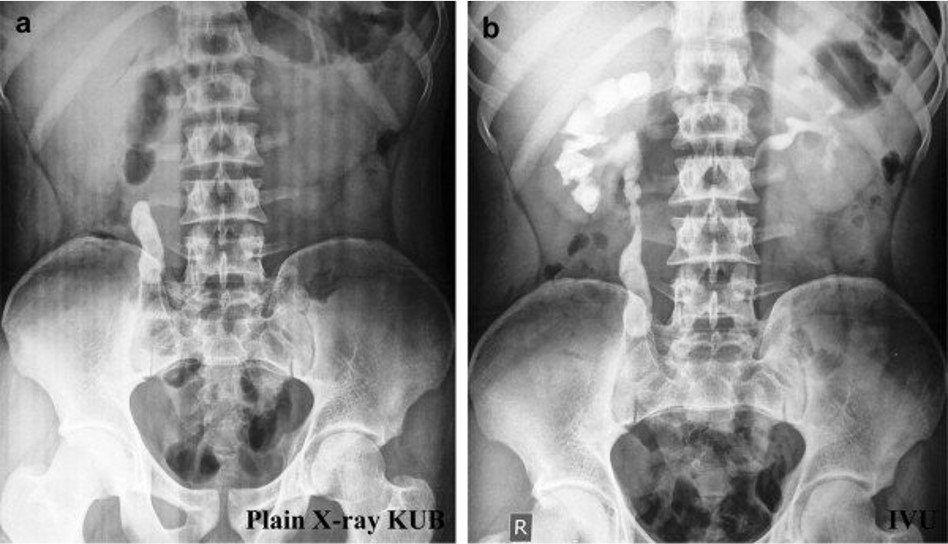

- Radiopaque stones appear as dense white opacities.

- Visibility depends on stone composition and size.

Stones Seen:

- Calcium oxalate, phosphate, struvite.

Stones Not Seen:

- Uric acid, xanthine, matrix stones.

a) Plain X-ray KUB showing a large radio-opaque density in the region of Right upper ureter, b) IVU shows presence of right upper ureteric calculus with prompt uptake and excretion of contrast from both renal units.